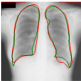

For the segmentation task, the inclusion of the saliency bridge module yields large improvements over the baseline U-Net and UMTL models. Again, with , we observed a 30% performance gain over its counterparts, which proves the effectiveness of our MultiMix model. The improvement in Dice scores of MultiMix with minimal supervision over the segmentation baselines of U-Net, UMTL, and UMTL-S is statistically significant (), confirming the quantitative efficacy of MultiMix. Figure 3 shows improved and consistent segmentation performance by the MultiMix model over the baselines. For a fair comparison, we used the same backbone U-Net and the same classification branch for all the models.

In Figure 4, the segmented lung boundary visualizations also show good agreement with the reference masks by MultiMix over the other models (also see Appendix B). For both the in-domain and cross-domain segmentations, we observe that the predicted boundaries are almost identical with the reference boundaries, as they substantially overlap. Moreover, the noise in the predictions is mitigated with the introduction of each additional component into the intermediate models, which justifies the value of those components in the MultiMix model. The good agreement between the ground truth lung masks and the MultiMix predicted segmentation masks is confirmed by the Bland-Altman plots for varying quantities of labeled data, shown in Figure 5(a).

Figure 9 shows the class-specific saliency maps generated by our MultiMix-50-1000 model for both in-domain and cross-domain classification data (). The maps consistently highlight particular regions in the input X-rays for the Normal and Pneumonia classes. Similarly, Figure 10 shows the saliency maps for the in-domain and cross-domain segmentation data (). While the class labels are not available, two distinct types of saliency maps are generated like for the classification data.

Class-specific saliency maps generated for images in consistently highlight regions responsible for predicting the particular classes of the images (Figure 9), enabling the use of these maps to improve the segmentation of images in (Figure 10).